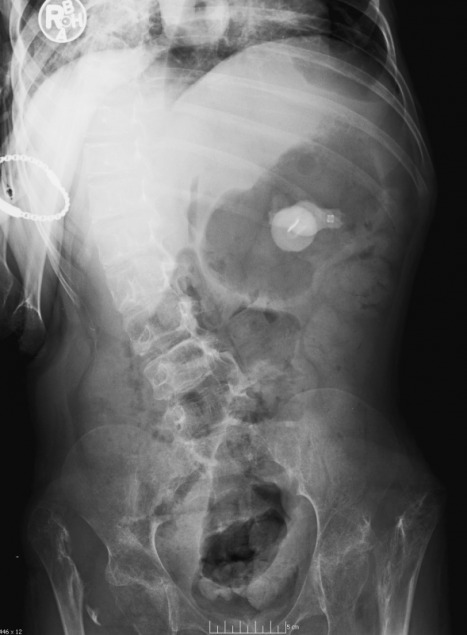

An obvious finding is the presence of light bulbs in the gastric region with prominent air in the stomach. Being that we’re entering the holiday season, this case is presented, in part, as a reminder to pay attention to children playing around with the decorations of the season.Looking beyond the foreign bodies in the stomach, the remaining findings include diffuse osteopenia and a right convex thoracolumbar scoliosis. Also noted are dysplastic changes at the hips bilaterally – the femoral heads and necks are not developed bilaterally and there are bilateral hip dislocations. The acetabula are also poorly formed bilaterally.

Differential diagnosis: At first guess, one might suggest bilateral developmental dysplasia of the hip (DDH) or perhaps proximal focal femoral deficiency (PFFD). However the differential needs to be expanded include disorders which may present with all 3 key findings - the scoliosis, osteopenia, and hip changes. This will include neuromuscular disease such as cerebral palsy and congenital disorders such as spondyloepiphyseal or spondylepimetaphyseal dysplasia. Neuromuscular disorders and dysplasia both have unique clinical features which may be useful for differentiation.

Diagnosis – Cerebral palsy (CP)

There are 4 traditional subtypes of CP, the most common of which is the spastic type. In spastic CP, changes in the skeleton are the sequelae of hypertonia which produces impaired neuromuscular mobility. The lack of the “normal” muscular stresses on the skeleton during development results in changes which primarily affect the spine and pelvis. Some patients with CP, as in this case, may show characteristics of Pica, the ingestion of foreign substances.